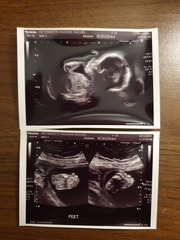

DaniX91 · 29/10/2019 18:41

How are u doing? The 20 week scan is amazing, so detailed 😍 we had ours a week and a half ago. I'll attach some pics x

Due March 2020 - FIRST BABY in late 20's